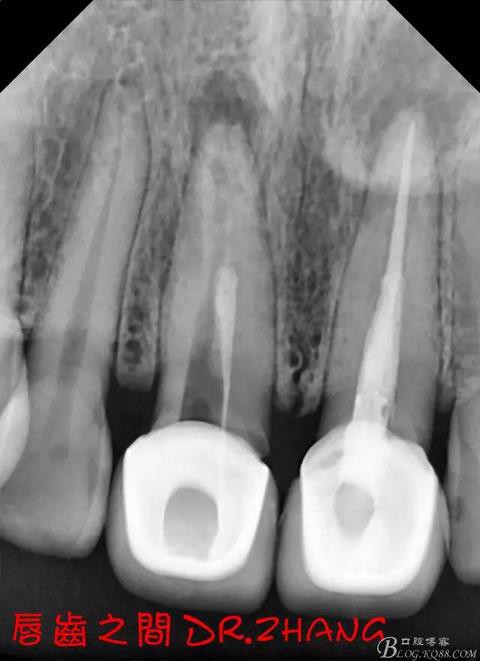

思博安熱牙膠系統(tǒng)根充 燙斷至根尖三分之一處后纖維樁恢復(fù)牙體組織

牙體預(yù)備后 硅橡膠取模 臨時牙恢復(fù)形態(tài)

復(fù)診:臨時牙良好 患者自訴無不適癥狀 去除臨時修復(fù)體 排齦 清理牙面 試戴全瓷修復(fù)體后粘結(jié) 常規(guī)醫(yī)囑 不適隨診